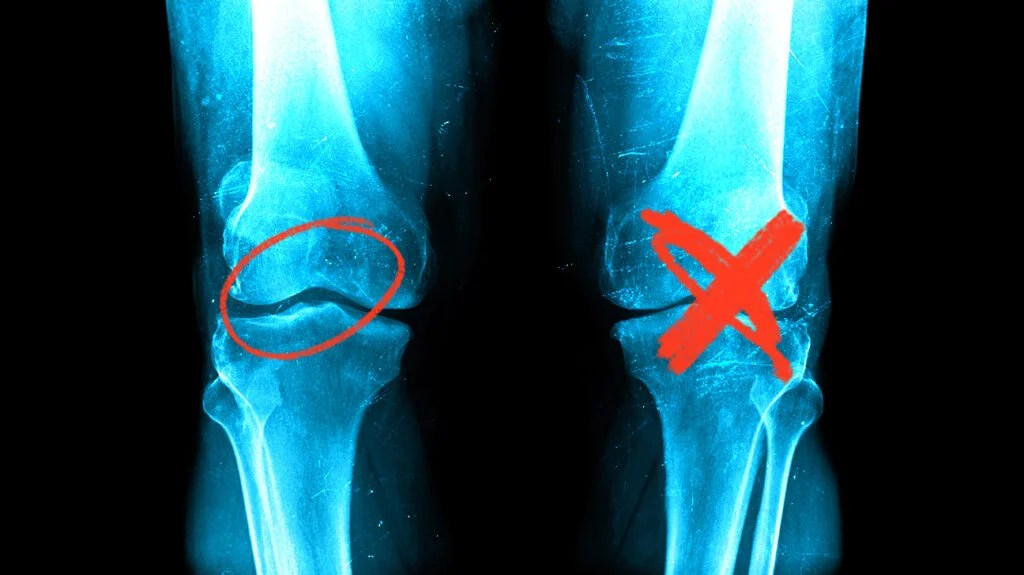

Joint Degeneration

The cartilage deficit: faster breakdown than rebuild

Healthy cartilage is in a constant state of turnover, old matrix proteins are broken down, new ones are synthesized. In young, healthy joints, this process stays roughly in balance. As we age, or as joints face repeated stress, two things happen simultaneously: the breakdown accelerates, and the synthesis slows down.

The result is a deficit that compounds over time. Each year of this imbalance means slightly thinner cartilage, slightly less cushioning, slightly more bone-on-bone friction on the worst days. The pain you feel is real tissue change, the joint sending you a signal that the deficit has grown large enough to cause damage.